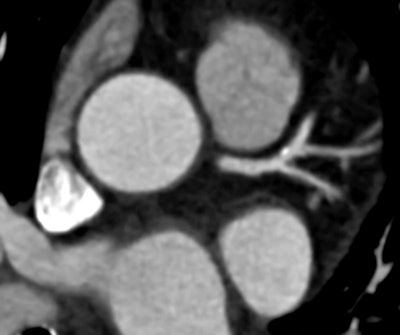

![]() |

| Compared to filtered back projection reconstruction (above), use of the iTRIM algorithm improves temporal resolution and renders a more diagnostic image. |